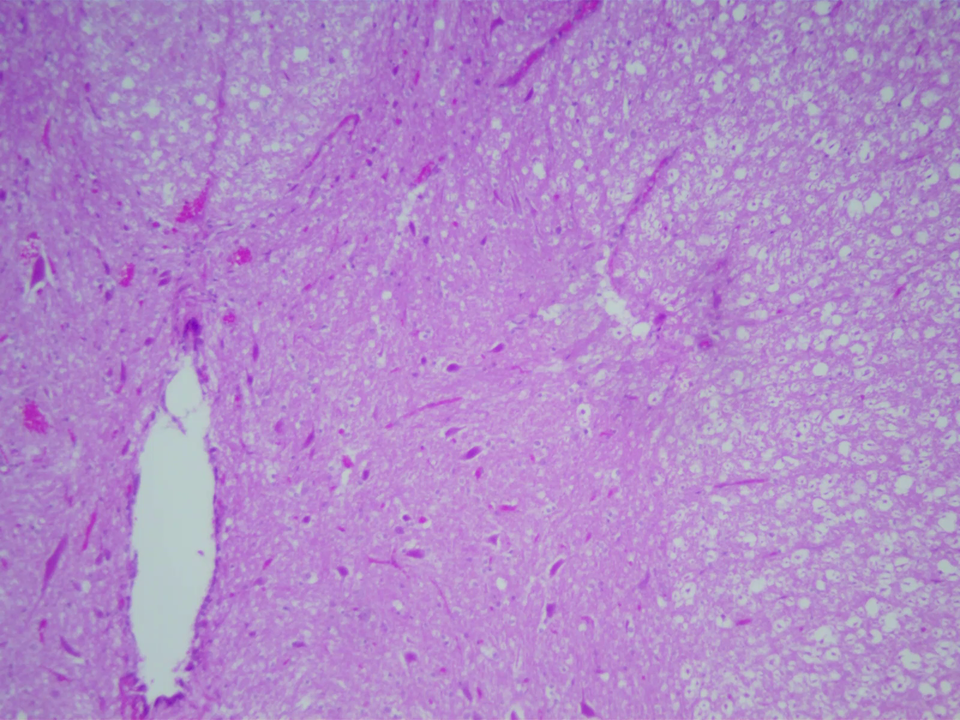

Za pomocą wirtualnego mikroskopu przeprowadzono obserwację przekroju poprzecznego przez rdzeń kręgowy. Rdzeń kręgowy zbudowany jest z istoty białej (wypustki neuronów), która otacza leżącą wewnątrz istotę szarą (skupisko ciał neuronów). Na przekroju poprzecznym istota szara (wybarwiona na ciemniejszy kolor) przybiera charakterystyczny kształt zbliżony do litery H. Jej pasma tworzą skierowane ku przodowi rogi brzuszne (przednie) oraz zwrócone ku tyłowi rogi grzbietowe (tylne). W centralnej części rdzenia kręgowego znajduje się kanał środkowy (wypełniony płynem mózgowo‑rdzeniowym). W powiększeniu czterokrotnym widoczna jest niewyraźnie struktura przypominająca kształt litery H lub skrzydła motyla. W środku struktury jest pionowy, biały, podłużny otwór, to kanał środkowy. Istotę szarą (literę H) wypełniają jasno- i ciemnoróżowe komórki. Wokół litery H jest istota biała. Wypełniają ją jasnoróżowe i białe komórki. W powiększeniu dziesięciokrotnym widoczna jest niewyraźnie górna część struktury przypominająca kształt litery H (lub skrzydła motyla), wypełniona drobnymi jasno- i ciemnoróżowymi komórkami. W środku struktury jest kanał środkowy. Jest on pionowy, biały, podłużny, a jego górny koniec jest wrzecionowaty. Wokół litery H znajduje się istota biała wypełniona jasnoróżowymi i białymi komórkami. W powiększeniu czterdziestokrotnym widoczna jest struktura wypełniona drobnymi jasno- i ciemnoróżowymi komórkami. Ciemnoróżowe komórki są kuliste, zebrane w skupiskach.